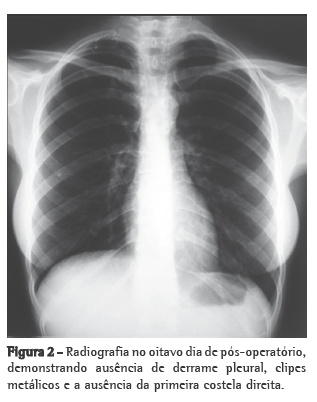

Após a reintervenção, a paciente evoluiu satisfatoriamente, com diminuição drástica da drenagem torácica, sendo introduzida uma dieta com triglicerídios de cadeia média no terceiro dia de pós-operatório e dieta livre a partir do sexto dia. No sétimo dia de pós-operatório, foi retirado o dreno torácico (Figura 2). A paciente recebeu alta hospitalar no oitavo dia de pós-operatório, apresentando dificuldade para elevar o membro superior direito. Após seis meses de acompanhamento com um programa fisioterápico adequado, a paciente encontrava-se com retorno total dos movimentos do membro superior direito. Os sintomas álgicos e de parestesia cessaram imediatamente após a cirurgia.